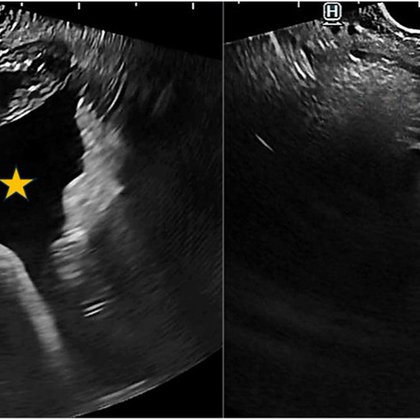

ESD ๐. 3cm BE with concerns for intramucosal ca on path removed en bloc. Excited to join @uams_GIHep and contribute to their already brilliant interventional endoscopy program @MaugarMD @SumantInamdar. Grateful to @shandrawes ๐๐ฝ๐๐ฝ๐๐ฝ @MuzaffarAkbar @Jean_Chalhoub @ASGEendoscopy